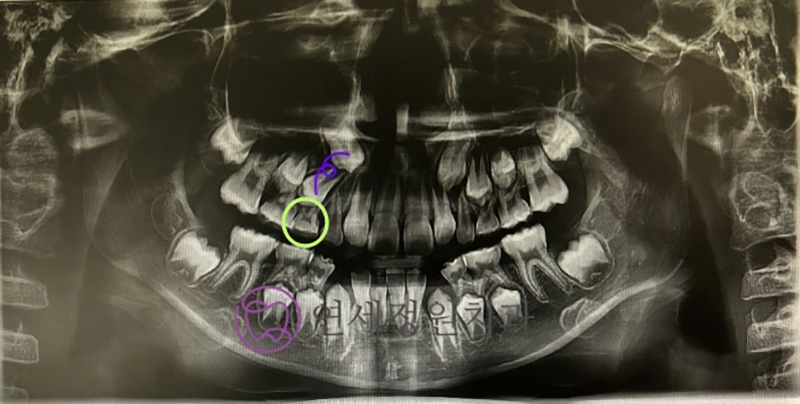

Because his baby teeth were coming out later than usual, I took a panoramic X-ray during a routine check-up. It showed that his upper right canine and first premolar were not aligned properly. The premolar was tilted backward, blocking the canine from erupting.

Even though his baby molar’s root was not yet resorbed, I decided to extract it early to help create space for the permanent tooth to come in.

Since the space couldn’t be maintained using a Band & Loop, we made a removable appliance that he wore only at night to keep the space open.

After about six months, his follow-up X-ray showed a much-improved eruption angle. He continued wearing the appliance for nearly a year, until the tooth finally erupted through the gums.